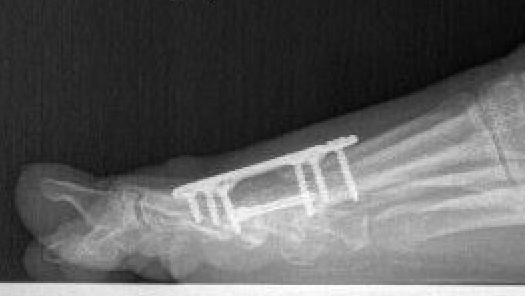

Arthrodesis

Indications

- hallux valgus with arthritis

- severe hallux valgus

- neuromuscular disease i.e. cerebral palsy

- rheumatoid arthritis

- salvage procedure for failed procedures

Technique

Fixation

- screws / plate / screws + plate